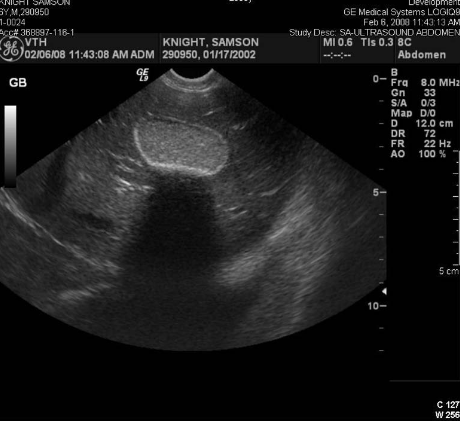

Liver

coarsely grained

large vessels, gallbladder is visible

diaphragm lies beneath the liver

portal veins have clearly defined, bright, hyperechoic walls

hepatic veins have poorly defined walls